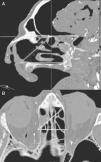

MethodsA descriptive study was performed including CT images of 20 cadaver heads. The specimens were perfused with a radiopaque material and various anatomical parameters were analysed.

ResultsThe anterior ethmoidal artery was found in 95% (38/40) of cases. It originated from the ophthalmic artery in 87.5% (34/40) of nasal cavities. In six cases, normal variants were found. The mean length of the anterior ethmoidal canal was 8.43±0.74mm. The angle performed into the skull base was 37.3±5.48°. In 90% of cases (36/40), it was located between the second and third lamella. The posterior ethmoidal artery was localised only in 14/40 cases, with 28.5% (4/14) of them showing normal variants. The mean length of the posterior ethmoidal canal was 7.1±1.02mm. The angle performed into the skull base was 7.11±4.07°. The distance from sill to the anterior ethmoid artery was 55.51±5.52mm. The angle between the nasal spine and the anterior ethmoidal canal was 57.67±1.68°. The distance between the nasion and the anterior ethmoidal canal was 29.31±2.53mm, the distance was 11.24±2.14mm from the anterior ethmoid artery to the posterior ethmoid artery and from the posterior ethmoid artery to the optic nerve, 7.26±1.33mm. Supraorbital cells were observed in 15% (6/40) of the cases.